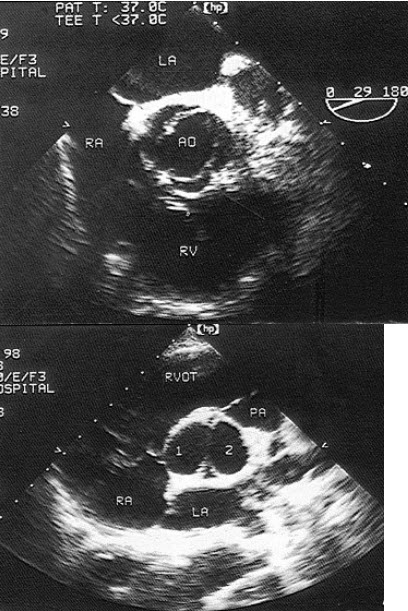

56、单项选择题 该肺动脉狭窄最可能为哪一型()

A.肺动脉闭锁

B.肺动脉瓣狭窄

C.肺动脉瓣下狭窄

D.肺动脉瓣上狭窄

E.肺动脉扩张